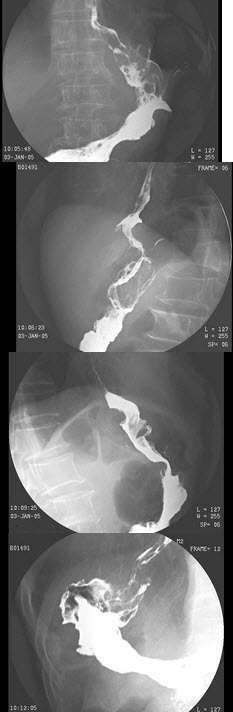

40、单项选择题

男,进行性吞咽困难1月余,结合图像,最可能的诊断为()

A.贲门失弛缓

B.食管癌

C.贲门癌

D.胃底癌

E.贲门癌侵及胃底

41、单项选择题

230、单项选择题

男,63岁,进行性吞咽困难1月。食管钡餐示:食管下段粘膜不规则充盈缺损,管腔狭窄,贲门扩张欠佳。

最可能的诊断是()

A.食管下段炎症

B.食管下段溃疡侵及贲门

C.食管下段癌侵及贲门

D.食管下段静脉曲张

E.以上都不对